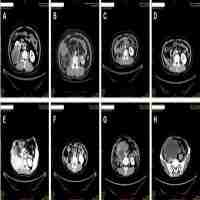

| Abstract | Perivascular epithelioid cell tumors (PEComas) are rare mesenchymal tumors. Unresectable malignant PEComas with TFE3 rearrangement have no recommended therapy to date. Here, we report the first case of malignant gastrointestinal PEComa with TFE3 rearrangement which has a response to the targeted therapy of an anti-VEGFR tyrosine kinase inhibitor (TKI), apatinib. A 31-year-old female was diagnosed with malignant gastrointestinal PEComa with TFE3 rearrangement and hepatic metastases. A resection of the giant retroperitoneal mass was performed. The patient received the anti-VEGFR TKI apatinib to treat the hepatic metastasis. The tumor remained stable during apatinib treatment and the progression-free survival (PFS) lasted about 7 months. This case suggests that targeting the VEGF/VEGFR signaling pathway may be an essential new therapeutic choice for TFE3-associated malignant PEComas. |